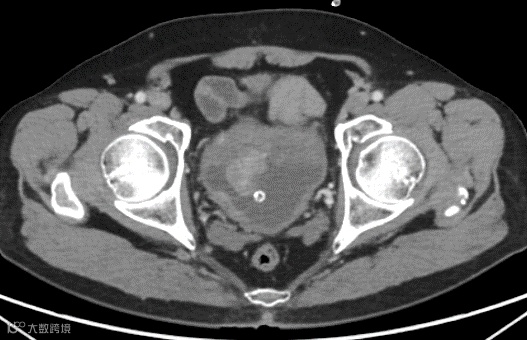

▲患者影像资料

本次手术患者60岁男性,以“血尿2月余”为主诉入院,经增强CT检查及病理会诊确诊为高级别浸润性尿路上皮癌,浸润固有层。经过仔细评估并结合患者病情及意愿,郑大一附院泌尿外科团队制定腹腔镜下膀胱根治性切除、盆腔淋巴结清扫+回肠代膀胱手术方案,并由张雪培教授远程实施。